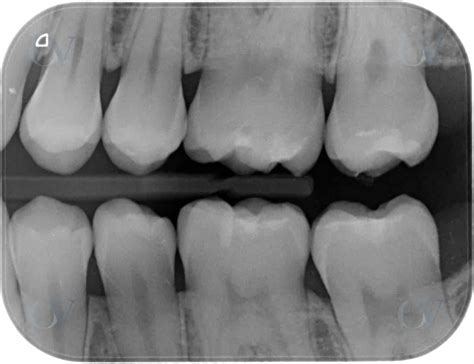

Caries interproximal en radiografías

- Detección de caries interdental: Las caries formadas entre los dientes suelen ser difíciles de detectar mediante una inspección visual, y con esta técnica se consiguen grandes resultados.

Una de las principales utilidades de la radiografía de aleta de mordida es la detección de caries interproximales, es decir, aquellas que se desarrollan en el espacio entre los dientes. La radiografía de aleta de mordida también es clave en la evaluación del hueso alveolar, es decir, el tejido óseo que sostiene los dientes en su lugar. La pérdida de altura ósea puede ser un signo temprano de enfermedad periodontal.